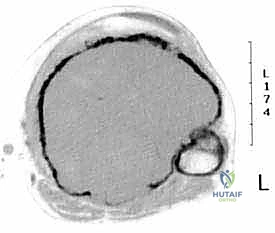

يقع المفصل الظنبوبي الشظوي القريب بالقرب من الجانب الخلفي الوحشي (الخارجي) للظنبوب القريب، وهو يربط بين عظم الظنبوب وعظم الشظية. تُظهر الدراسات النسيجية والباثولوجية المتقدمة أن الأورام الخبيثة التي تصيب الظنبوب القريب غالباً ما لا تحترم الحدود التشريحية، وتمتد لتشمل الأنسجة المحيطة بهذا المفصل الصغير.

لذلك، وفي قاعدة جراحية ذهبية للحصول على "هامش جراحي آمن" (Safe Surgical Margin) وخالٍ تماماً من الخلايا السرطانية، من الضروري إزالة هذا المفصل بالكامل كوحدة واحدة (En Bloc Resection) مع الظنبوب المصاب وعظم الشظية القريب. هذه العملية تُعرف بالاستئصال خارج المفصل (Extra-articular Resection)، وهي تضمن عدم ترك أي خلايا ورمية مجهرية قد تؤدي إلى انتكاس المرض وعودته في المستقبل.